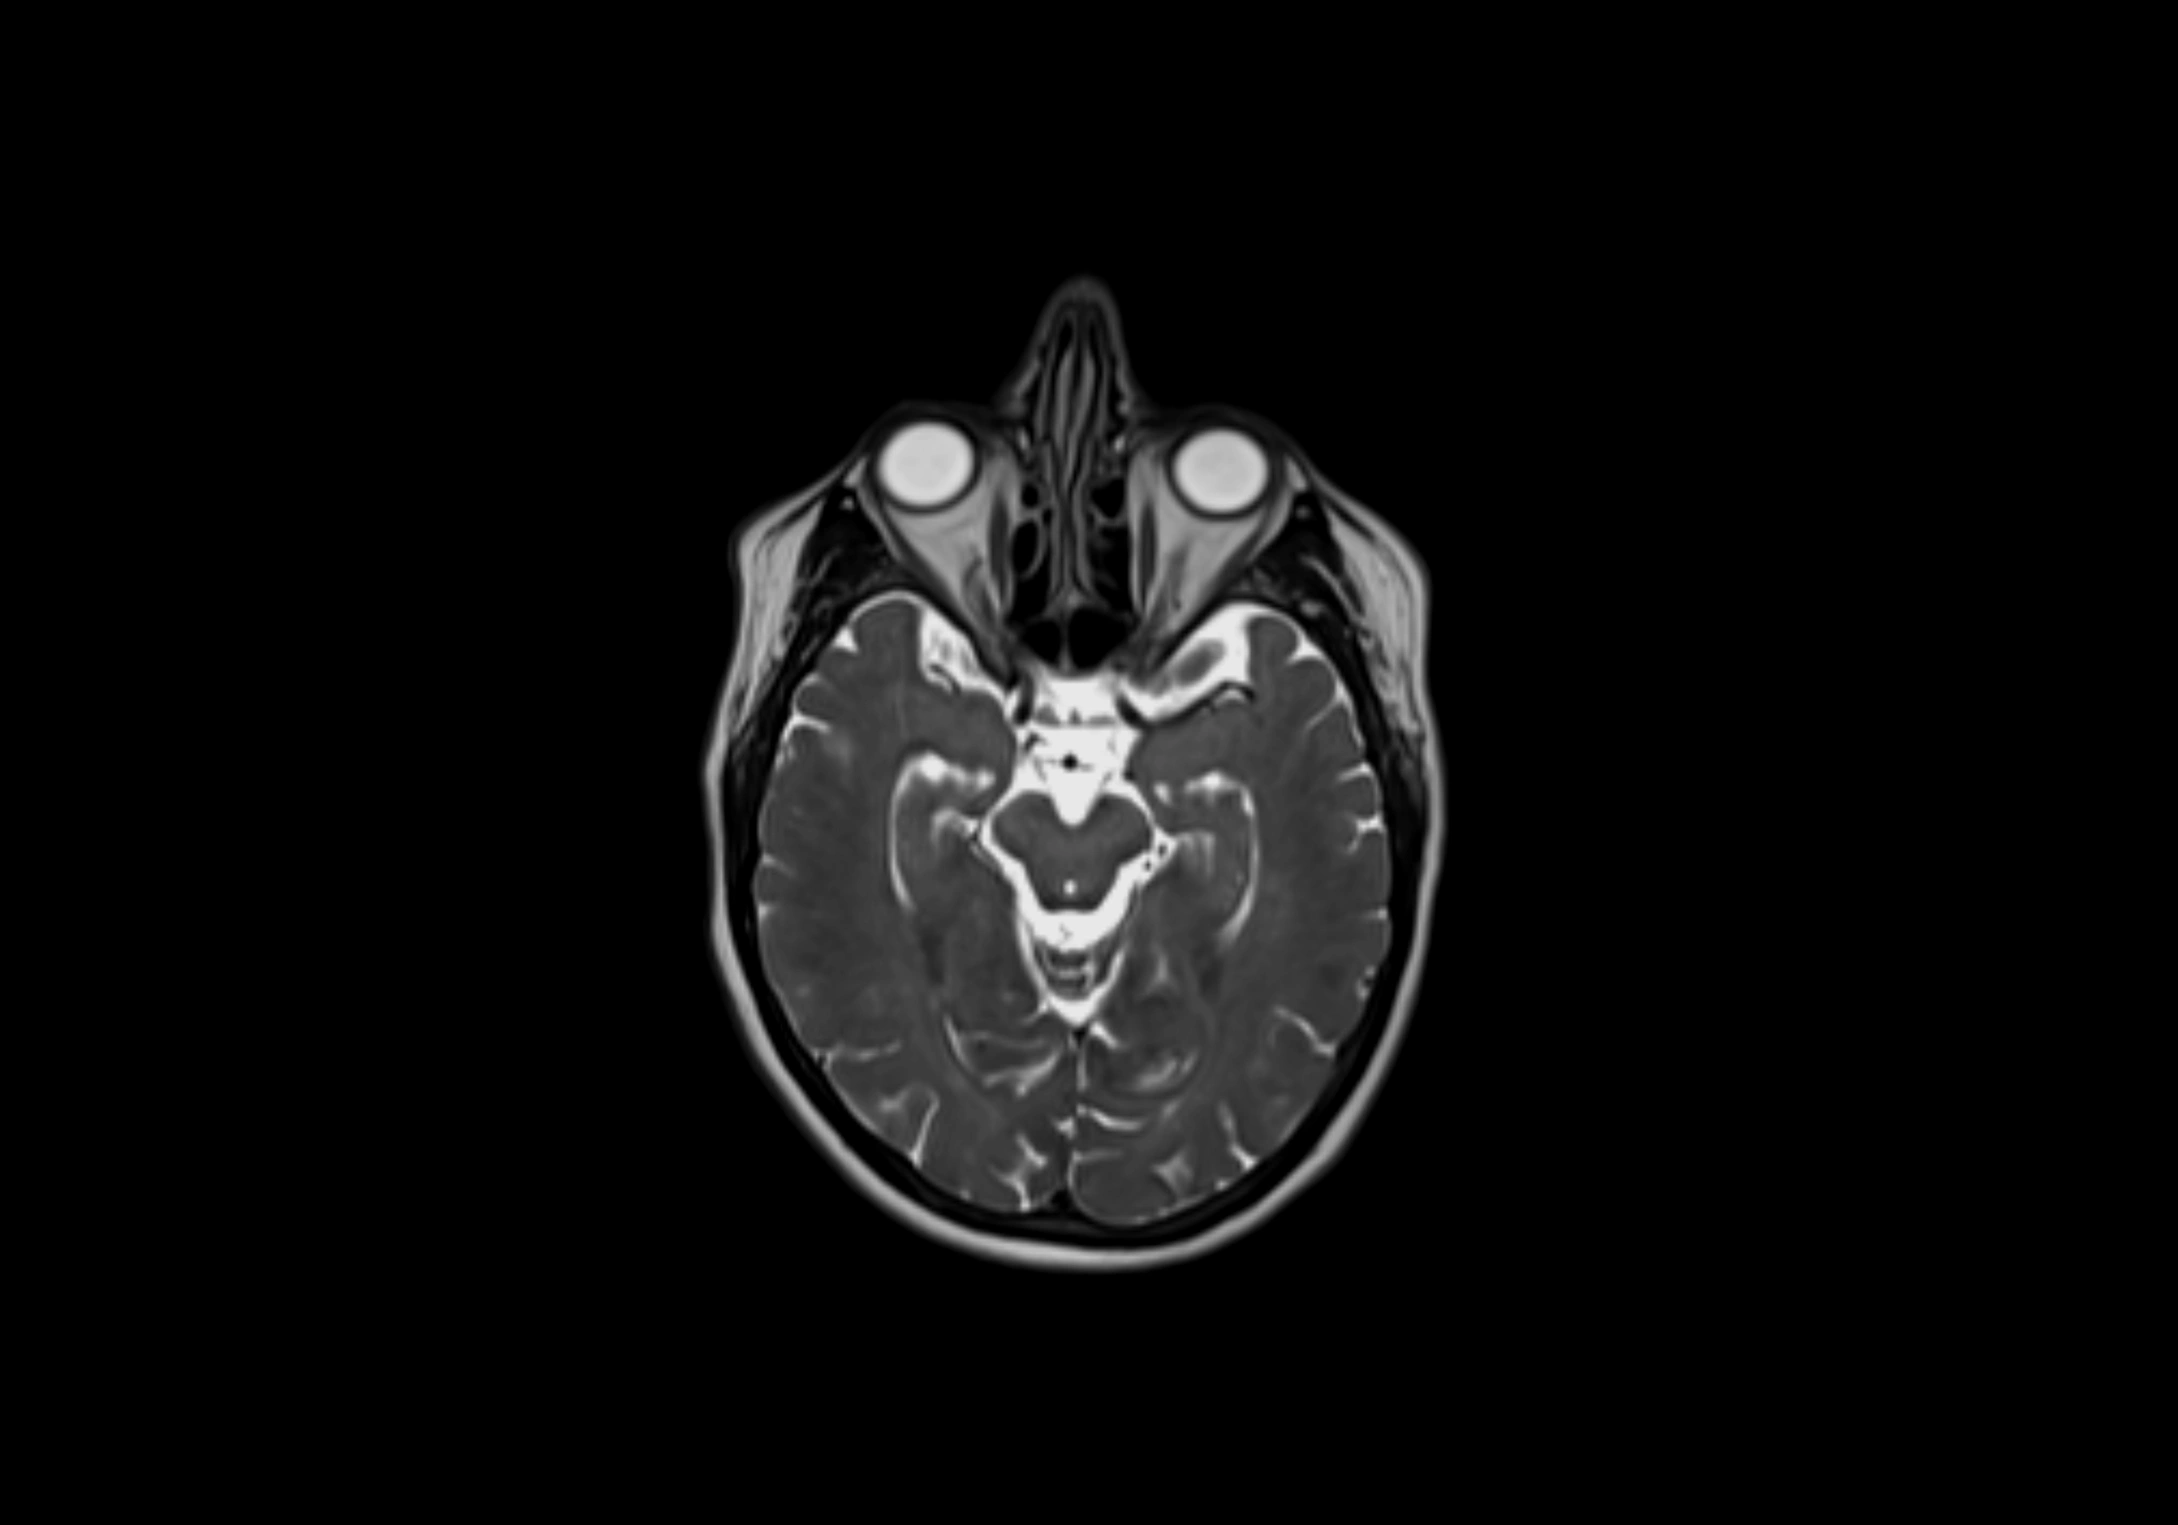

MRI Appearance

T1-weighted images:

• Normal accessory nodes appear as small, oval hypointense to intermediate signal structures within subcutaneous fat

• Surrounded by hyperintense fat, enhancing contrast for visualization

• Pathological nodes may appear enlarged or rounded, sometimes with cortical thickening

T2-weighted images:

• Nodes show intermediate signal, with surrounding fat bright

• Useful for detecting edema, inflammation, or infiltration

• Fatty hilum may appear slightly hyperintense relative to cortex